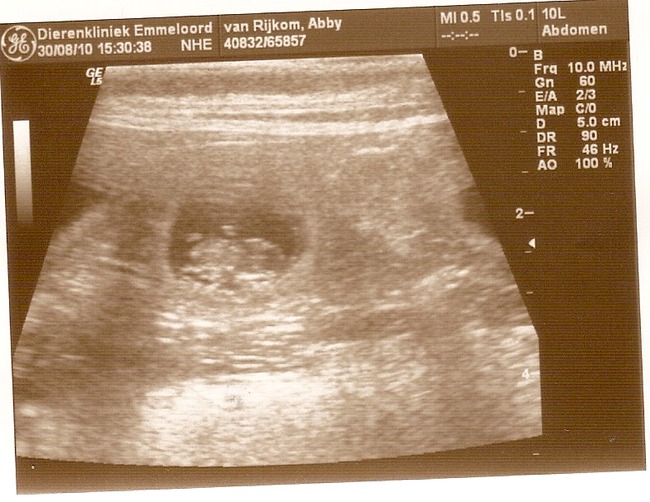

Onze vermoedens zijn bevestigd, Abby is inderdaad drachtig! En hoe...

Op de echo waren 7 levende pups met mooie kloppende hartjes te zien!!!

Hier trouwens de echo foto's:

Oh beetje een kleine foto... Ik zal kijken of ik 'm groter kan plaatsen

We zeiden ook al bij 5 jullie mogen nu wel stoppen hoor maar het ging maar door en door, we hebben allemaal echt iets van 3x getelt en steeds kwamen we op die schrikbarende 7 pups uit

Ja het blijft afwachten, ze kunnen altijd een foutje maken bij zo een echo. Maar heb meegeteld en er ook 7 gezien dus zal spannend worden